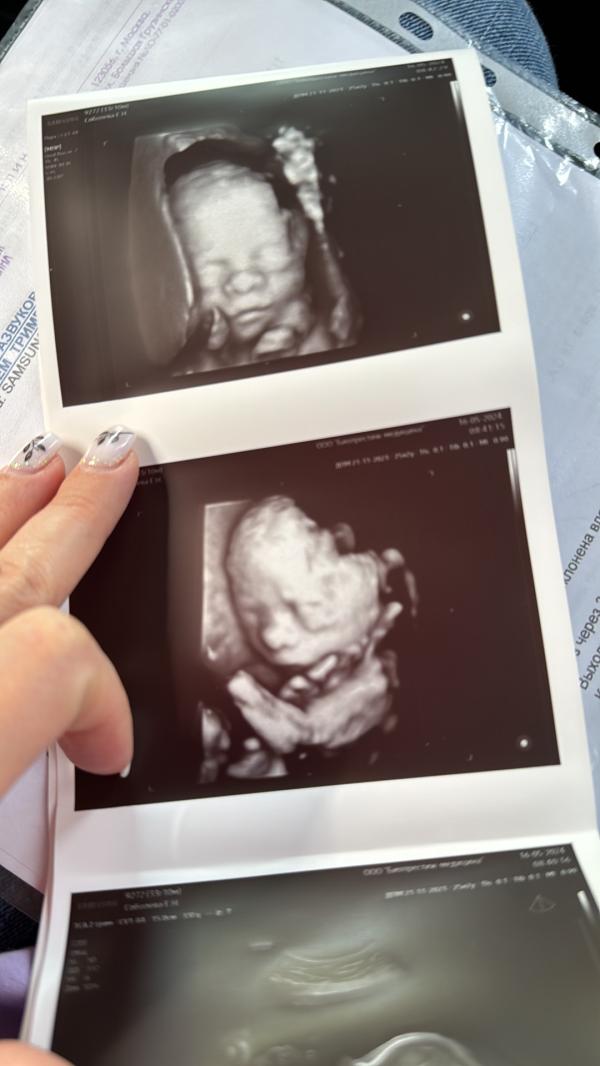

Ну что)была я сегодня на узи,на счет предлежания плаценты.Поднялась моя плацента высоко,выше 7 см,можно выдыхать)малышка чувствует себя отлично)весим 700 гр и 30 см)сказали миниатюрная!Была я у ТЁ!!Шикарный врач!!!К нему записалась на 32 недели уже

У вас так хорошо малышка получилась на 3д узи, показала свое лицо, а у нас пряталась 🤣

@katya_steshaaa, закрылась да,ну носик торчит и губки))моя там вся вертелась,вот и поймали,и мое узи кажется в 4д было

Это еще так на бумажке)еще и фото и видео в цвете на вот сап пришлют)это у доктора ТЁ (большая грузинская 39)Биопрестиж Медицина 7000